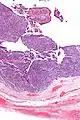

| Micrograph of transitional cell carcinoma of the ovary. H&E stain. |

TCC of the ovary is diagnosed by examination of the tissue by a pathologist. It has a characteristic appearance under the microscope and distinctive pattern of immunostaining.[2]